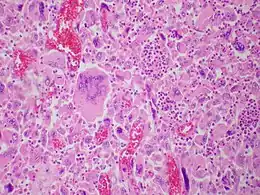

Description de l'image Giant cell carcinoma - Case 284 (13107156794).jpg.

Le carcinome pulmonaire à cellules géantes est un sous-type de carcinome pulmonaire à grandes cellules (ou carcinome anaplasique à grandes cellules).